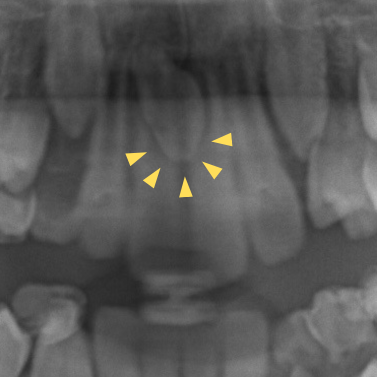

それぞれ以下のような状態です。

正中埋伏過剰歯